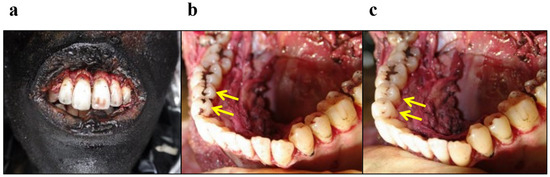

4.3.2. Cases of Misidentification of Primary Molars as Molars Because of Narrow Opening of the Mouth